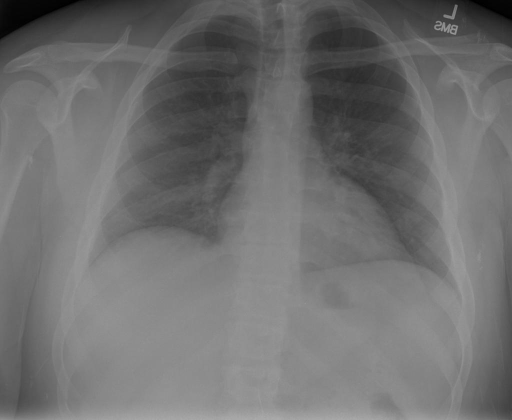

|X光影像|诊疗报告(医生)|XrayGLM|

|:-|:-|:-|

||心影形态在正常范围内。没有急性骨质异常。有可能出现没有明显的吸水或肺实质状况的线索。没有大面积积液或气胸。有可能怀疑其有误吸或肺实质问题。为了确诊和治疗,可能需要进行适当的影像学随访。|心脏大小正常,肺部和纵隔轮廓清晰。没有急性异常或活动受限的证据。没有任何明显的气胸、胸腔积液或肺不张的迹象。此外,也没有发现任何局灶性骨质异常或其他急性疾病。|